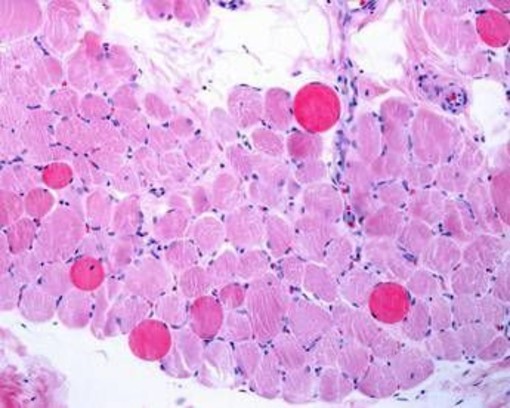

(Adnkronos) - Sono positivi i risultati di un'analisi dei dati a lungo termine - comprese le prime valutazioni dello studio multicentrico in aperto Guardian, attualmente in corso - che valuta Agamree* (vamorolone) in pazienti affetti da distrofia muscolare di Duchenne (Dmd). Lo annuncia in una nota Santhera Pharmaceuticals, precisando che l'analisi ha incluso pazienti mai trattati con corticosteroidi e che hanno iniziato il trattamento con Agamree tra i 4 e i 7 anni di età nell'ambito di studi clinici, proseguendo poi attraverso vari programmi di accesso tra cui lo studio Guardian.

Sono stati analizzati i dati di un massimo di 110 pazienti, con un numero variabile in base alla disponibilità delle informazioni. In questa analisi i pazienti avevano ricevuto il trattamento per un massimo di 8 anni, con un follow-up mediano di circa 5 anni. La maggior parte dei pazienti ha mantenuto dosi elevate (4-6 mg/kg/giorno) in contesti clinici di real world durante il periodo di osservazione. I risultati mostrano che i pazienti trattati con vamorolone hanno mantenuto la funzione motoria durante il follow-up prolungato, dimostrando un'efficacia duratura del trattamento misurata in base al tempo di perdita della deambulazione paragonabile a quella dei corticosteroidi standard (p=0,91). Nelle analisi di sottogruppi prestabilite non sono state osservate differenze rispetto al deflazacort o al prednisone assunti quotidianamente. I dati - riporta l'azienda - continuano a confermare un profilo di sicurezza e tollerabilità differenziato rispetto ai corticosteroidi tradizionali. I pazienti trattati con Agamree hanno registrato un tasso significativamente inferiore di fratture vertebrali (p=0,0061), hanno mantenuto una crescita normale senza il rallentamento osservato con i corticosteroidi standard (p<0,0001) e hanno mostrato un numero inferiore di casi di cataratta rispetto ai pazienti trattati con glucocorticoidi, compresa un'incidenza notevolmente inferiore rispetto ai pazienti trattati con deflazacort (p<0,015). Inoltre, a oggi, non sono stati osservati casi di glaucoma. In media, le variazioni dell'indice di massa corporea o del peso, se rapportate all'altezza, non hanno mostrato differenze e non sono stati osservati nuovi segnali di sicurezza.